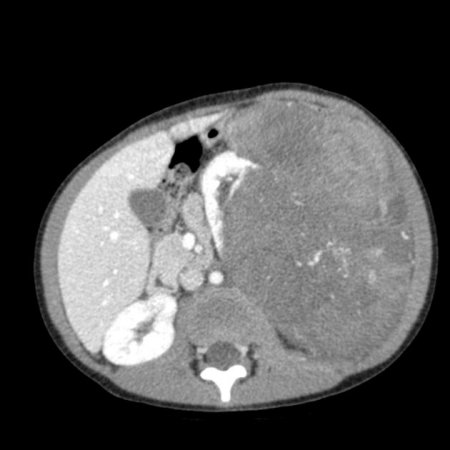

- Компьютерная томография органов брюшной полости и забрюшинного пространства с оральным и внутривенным контрастированием (см. рис. 1).

Рисунок 1. КТ брюшной полости ребенка с большой нефробластомой с метастазами в печень.

Рисунок 2. КТ: опухоль при поступлении. Клинически: при пальпации опухоль в проекции правой почки до 12 см в диаметре. Общеклинические исследования в пределах возрастной нормы. При КТ органов брюшной и грудной полости: КТ-картина объемного образования правой почки без признаков интрапульмональных метастазов (см. рис. 2). УЗИ брюшной полости: в проекции правой почки солидно-кистозное образование 101ґ114ґ99 мм, объемом 500 мл, васкуляризация активная, интактная часть почки 57ґ12ґ40 мм. Объемное образование правой почки — опухоль Вильмса. Предварительный диагноз: опухоль Вильмса правой почки, 2-я стадия.